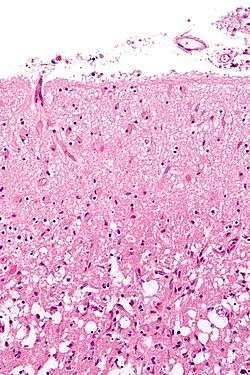

Glial scar formation (gliosis) is a reactive cellular process involving astrogliosis that occurs after injury to the Central Nervous System. As with scarring in other organs and tissues, the glial scar is the body's mechanism to protect and begin the healing process in the nervous system.

Reactive astrocytes are the main cellular component of the glial scar.[2] After injury, astrocytes undergo morphological changes, extend their processes, and increase synthesis of glial fibrillary acidic protein (GFAP). GFAP is an important intermediate filament protein that allows the astrocytes to begin synthesizing more cytoskeletal supportive structures and extend pseudopodia. Ultimately, the astrocytes form a dense web of their plasma membrane extensions that fills the empty space generated by the dead or dying neuronal cells (a process called astrogliosis). The heavy proliferation of astrocytes also modifies the extracellular matrix surrounding the damaged region by secreting many molecules including laminin, fibronectin, tenascin C, and proteoglycans.[3][4] These molecules are important modulators of neuronal outgrowth. Accordingly, their presence after injury contributes to inhibition of regeneration.[5][6]

The basal membrane is a histopathological extracellular matrix feature that forms at the center of injury and partially covers the astrocytic processes. It is composed of three layers with the basal lamina as the prominent layer. Molecularly, the basal membrane is created by glycoprotein and proteoglycan protomers. Further, two independent networks are formed within the basal membrane by collagen IV and laminin for structural support. Other molecular components of the basal membrane include fibulin-1, fibronectin, entactin, and hepparan sulfate proteoglycan perlecan. Ultimately, the astrocytes attach to the basal membrane, and the complex surrounds the blood vessels and nervous tissue to form the initial wound covering.[2]